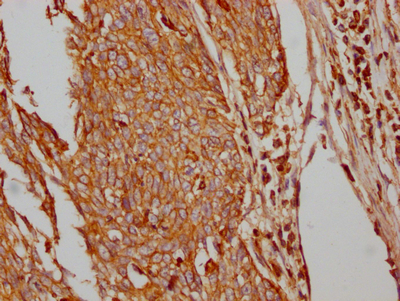

• IHC image of CSB-RA297401A0HU diluted at 1:100 and staining in paraffin-embedded human cervical cancer performed on a Leica BondTM system. After dewaxing and hydration, antigen retrieval was mediated by high pressure in a citrate buffer (pH 6.0). Section was blocked with 10% normal goat serum 30min at RT. Then primary antibody (1% BSA) was incubated at 4℃ overnight. The primary is detected by a Goat anti-rabbit IgG polymer labeled by HRP and visualized using 0.05% DAB.

Validation in immunohistochemistry demonstrates reliable performance in paraffin-embedded human tissue sections. Testing in both cervical cancer and lung cancer specimens at 1:100 dilution confirms the antibody's utility for studying GLUT1 expression in tumor microenvironments, with citrate buffer antigen retrieval providing optimal signal. The recommended working range of 1:50 to 1:200 allows flexibility for optimization across different tissue types and detection systems. Additional compatibility with ELISA extends its utility for quantitative applications.